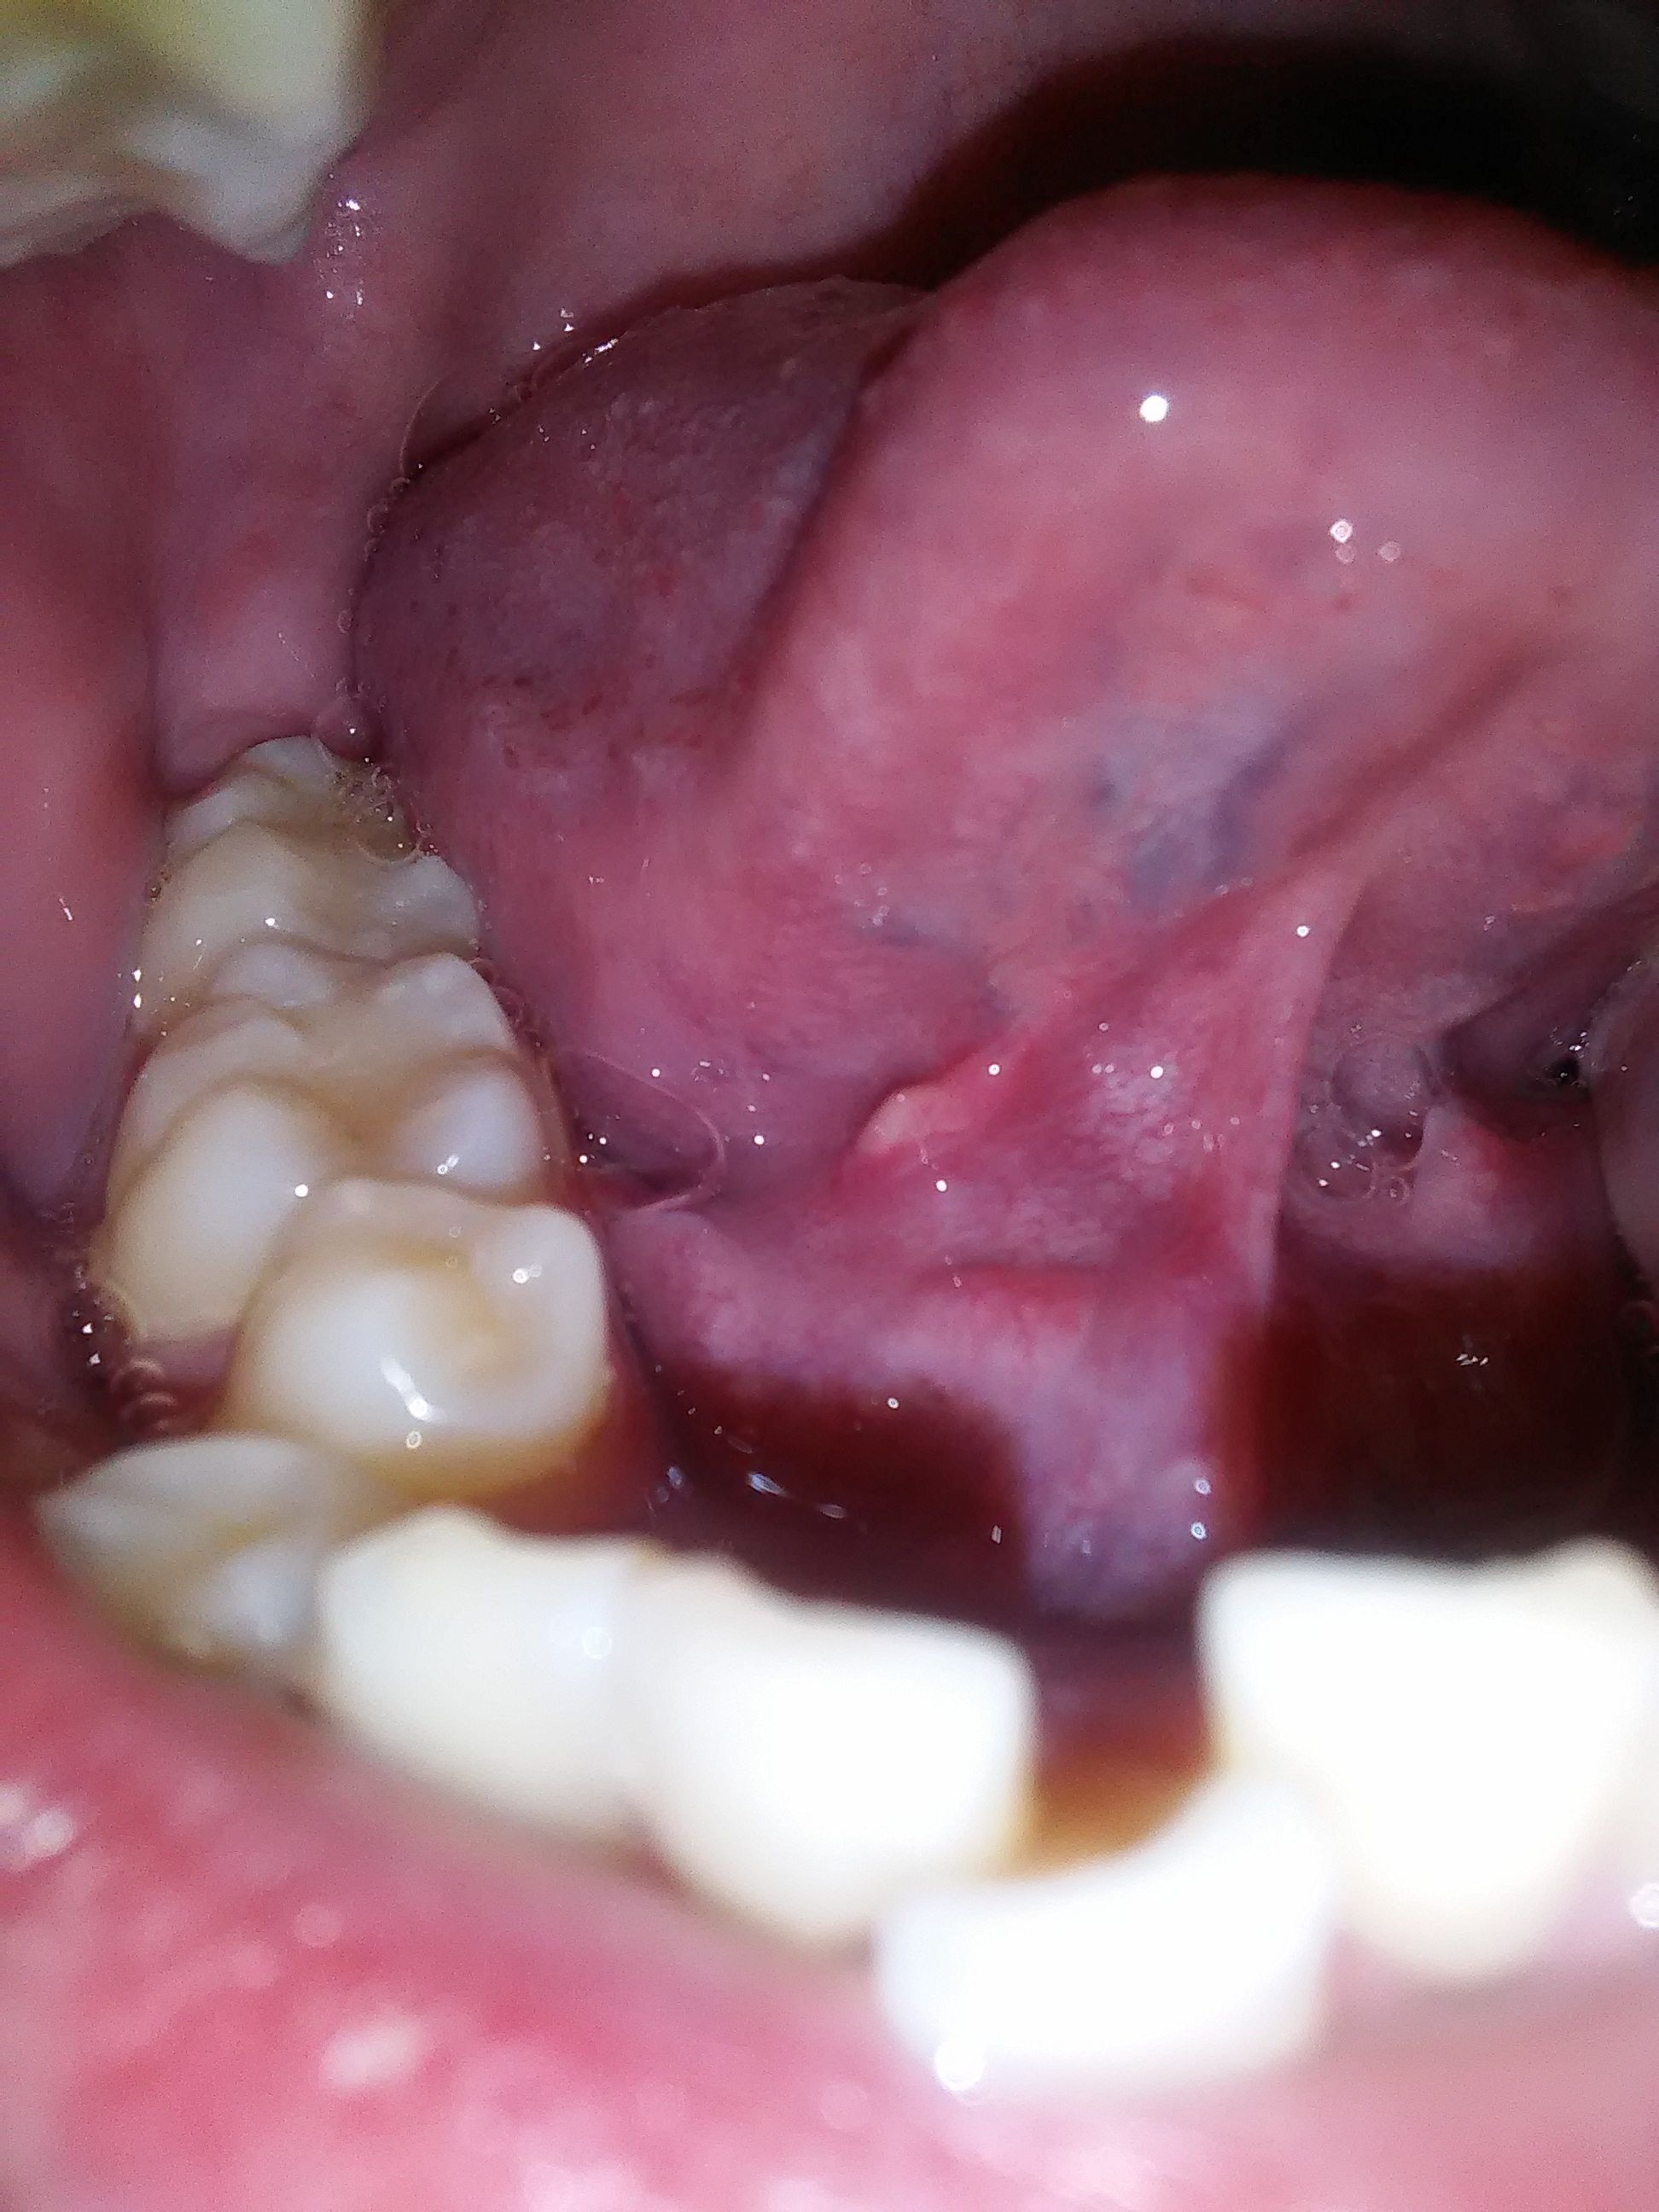

舌头下面长的肉芽不痛不痒不注意感觉不到

1、上火生活习惯不规律饮食不健康等可能导致上火,从而引发舌头底下长肉芽的情况此时,可以尝试服用下火药,多喝水,并保持规律的作息和生活习惯唾液腺囊肿这也是一种可能的原因如果没有明显不适,可以暂不处理如有不适,建议前往正...